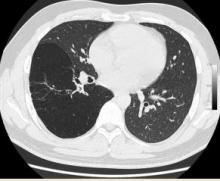

A 35-year-old male was admitted to our department for surgery having been diagnosed with CCAM and bronchial atresia. A CT scan showed a cystic lesion in the right lower lobe according to CCAM (Figure 1). Bronchoscopy revealed absence of segment 6 bronchus. He had been suffering from recurrent pneumonias since childhood. Due to persistent symptoms he was offered lung resection by video-assisted thoracoscopic surgery (VATS). The entire lower lobe was transformed into a huge cyst, so a right lower lobectomy was performed through a single 4 cm incision with no rib spreading.

Figure 1. CT scan showing a huge cystic lower lobe.